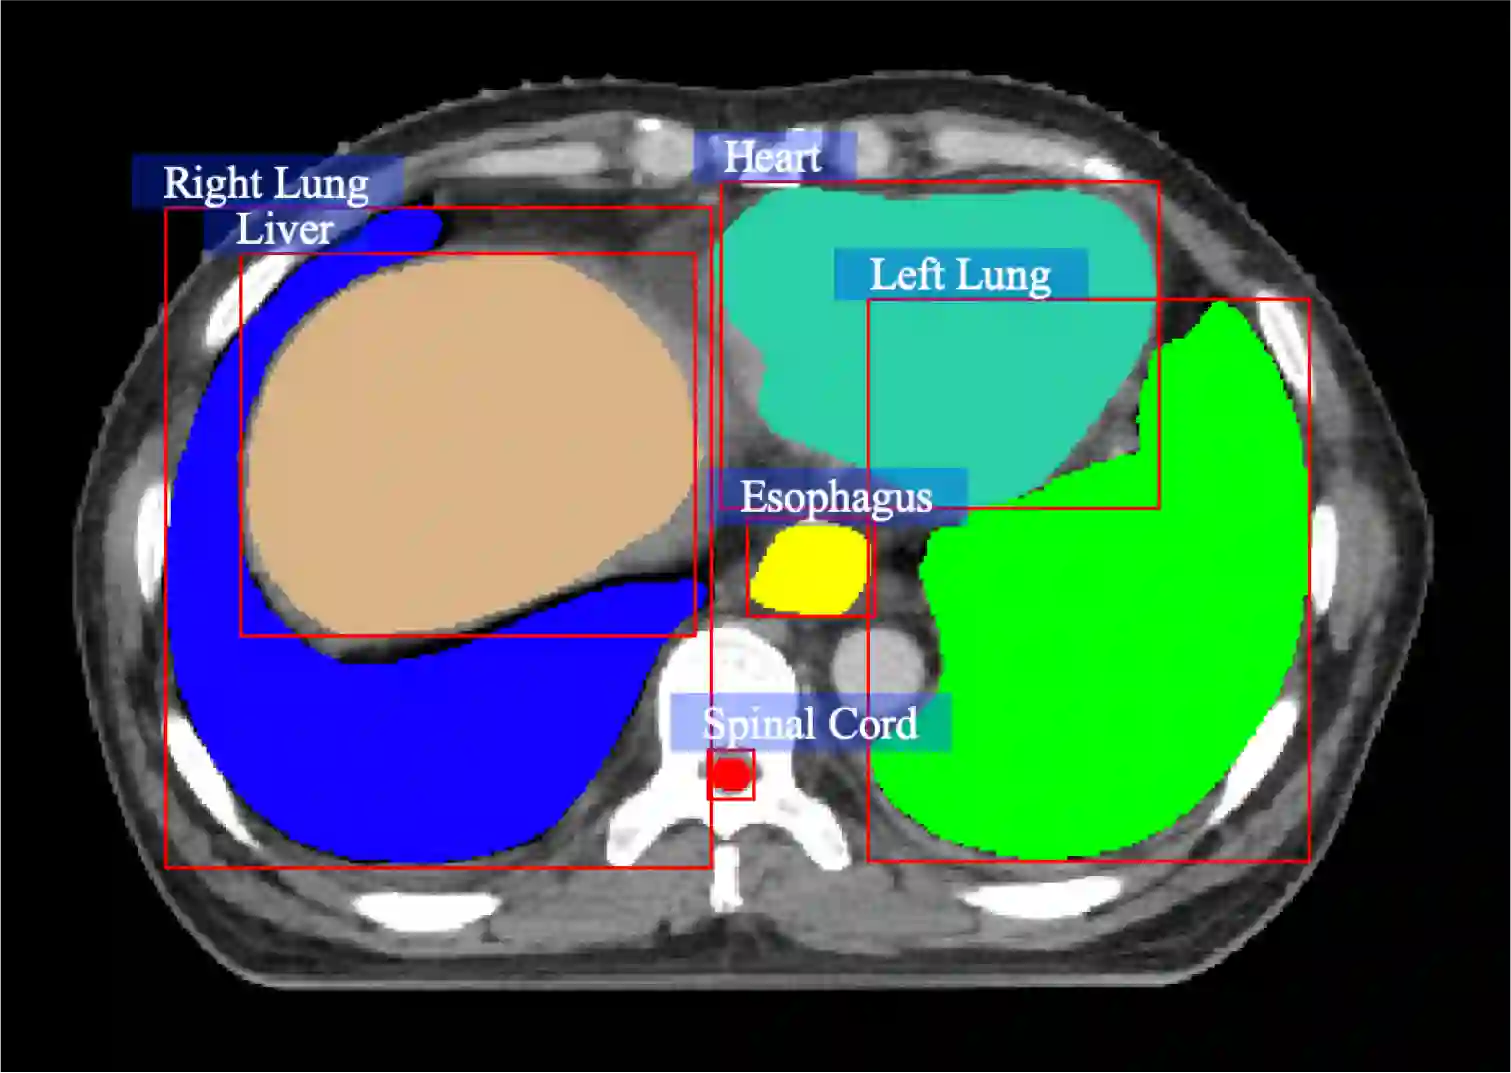

Medical visual question answering (Med-VQA) has tremendous potential in healthcare. However, the development of this technology is hindered by the lacking of publicly-available and high-quality labeled datasets for training and evaluation. In this paper, we present a large bilingual dataset, SLAKE, with comprehensive semantic labels annotated by experienced physicians and a new structural medical knowledge base for Med-VQA. Besides, SLAKE includes richer modalities and covers more human body parts than the currently available dataset. We show that SLAKE can be used to facilitate the development and evaluation of Med-VQA systems. The dataset can be downloaded from http://www.med-vqa.com/slake.